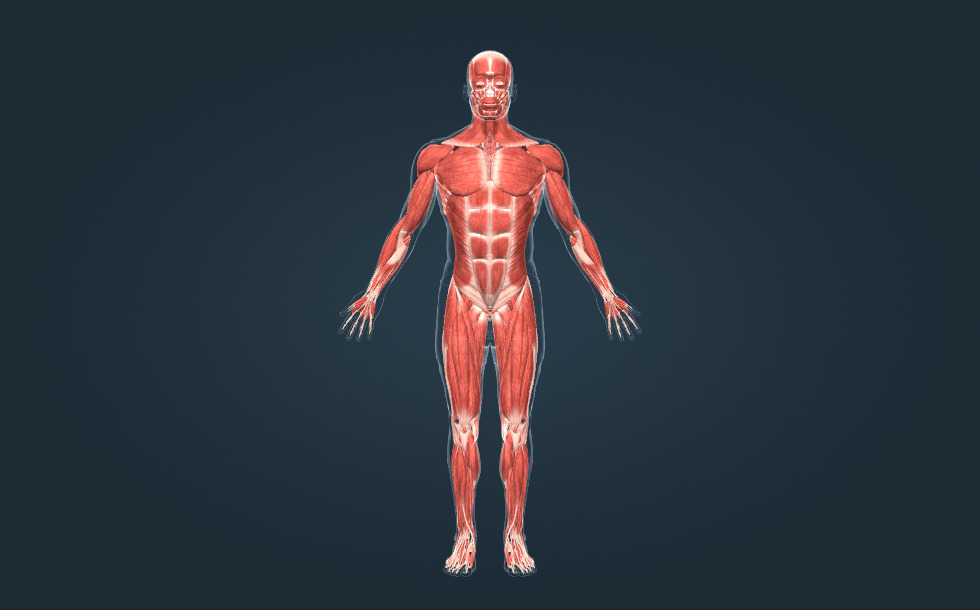

Músculos esqueléticos

- músculos de la cabeza

- músculos del pecho

- músculos abdominales

- músculos de la pantorrilla

- músculos del cuello

- músculos del brazo

- músculos del antebrazo

- músculos del muslo

- músculos de la espalda

Los músculos esqueléticos son los órganos principales de locomoción. Hay aproximadamente 350 músculos esqueléticos en el cuerpo humano, que pueden componer el 50 % de la masa corporal. Existen músculos largos, cortos, aplanados y en forma de anillo. Los músculos se unen a los huesos mediante tendones.

Los músculos esqueléticos son los órganos principales de locomoción. Hay aproximadamente 350 músculos esqueléticos en el cuerpo humano, que pueden componer el 50 % de la masa corporal. Existen músculos largos, cortos, aplanados y en forma de anillo. Los músculos se unen a los huesos mediante tendones.